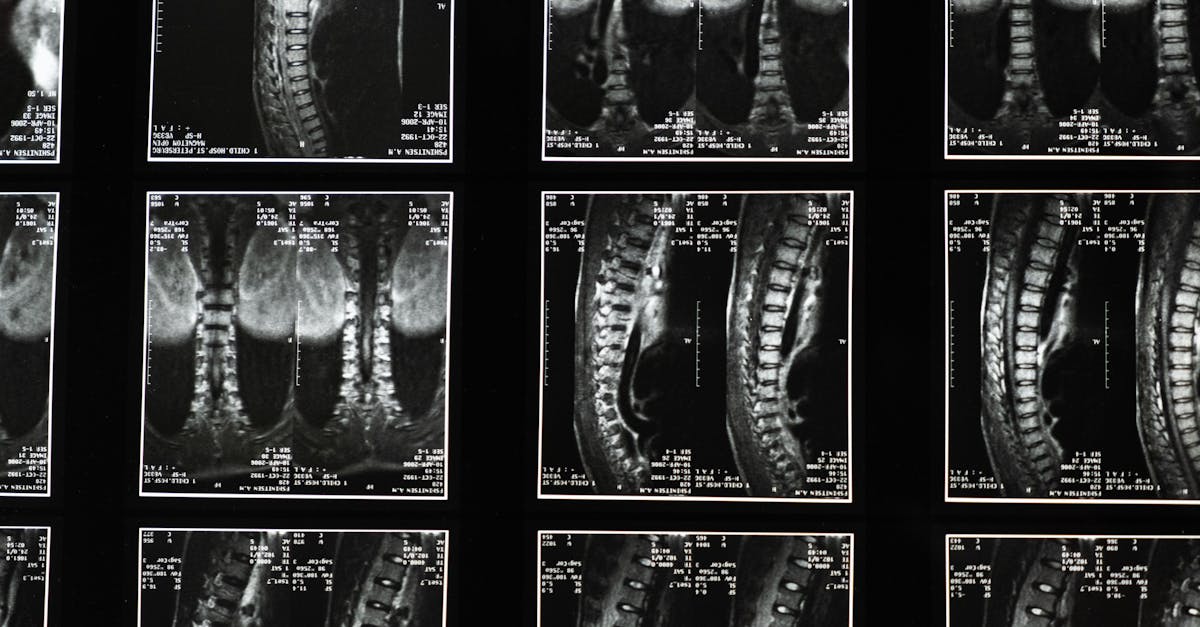

- Imaging and testing: Structural findings on imaging (when performed) don’t always perfectly predict symptoms, so care decisions are based on a combination of history, exam, and, when needed, imaging results.

- Share any prior imaging results (X-ray, MRI, CT) or diagnoses related to your spine or nerves.